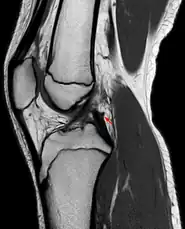

Posterior meniscofemoral ligament on MRI, sagittal

The posterior meniscofemoral ligament (also known as the ligament of Wrisberg) is a small fibrous band of the knee joint. It attaches to the posterior area of the lateral meniscus and crosses superiorly and medially behind the posterior cruciate ligament to attach to the medial condyle of the femur.[1]

The posterior meniscofemoral ligament is found in 64.4% of the subjects in MRI scan of the knee.[1]